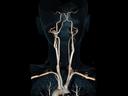

More and more radiologists are relying on the rich diagnostic possibilities offered by True Dual Energy imaging on Siemens Healthineers' CT scanner fleet ranging from SOMATOM® Scope Power up to the outstanding SOMATOM Force.

The question is: What makes True Dual Energy stand out? Look for these three criteria: crisp images with the option for even sharper contrast and significant artifact reduction; no extra dose in either Single Source or Dual Source Dual Energy scans, and a broad applicability for virtually all clinical questions and patients.

Discover Dual Energy (DE) spectral imaging. It’s the difference between images and answers. Visualization and characterization. Qualification and quantification. Built into all of our CT scanners, it delivers powerful performance, incredible versatility for your entire patient population, and exceptional ease-of-use – all while integrating seamlessly with your current workflow.